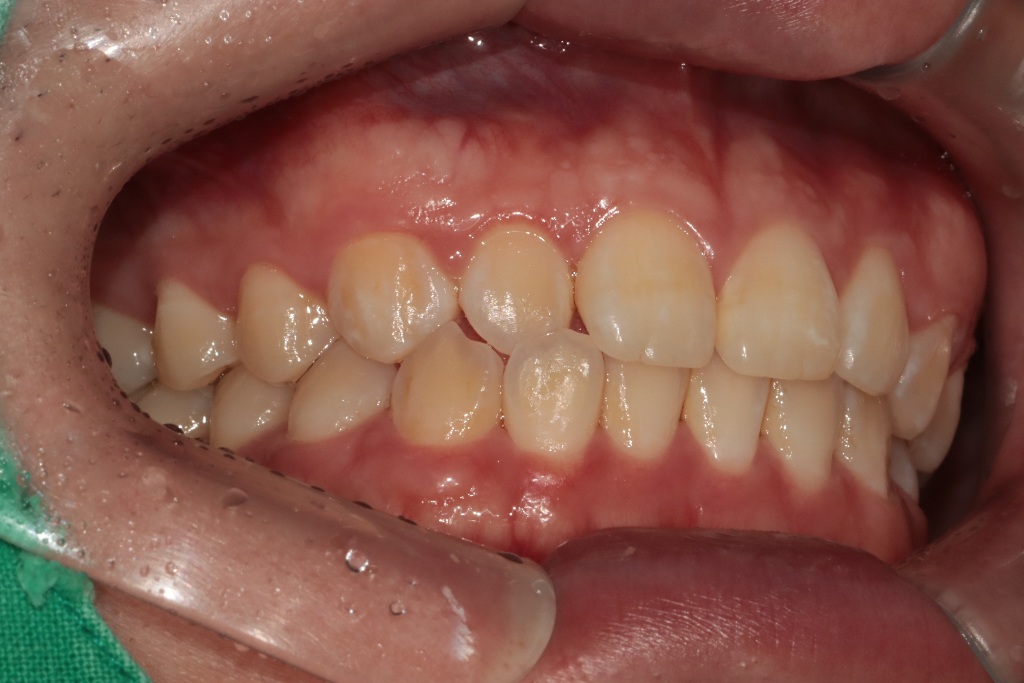

상악이나 하악이 정상범주에서 벗어났나요?

1.상악이나 하악이 정상범주에서 벗어났나요?

1. 상악과 하악을 비교했을 때, 상악 저성장으로 보입니다. 다만 정확한 것은 교정치과 방문 후 상담이 필요합니다.